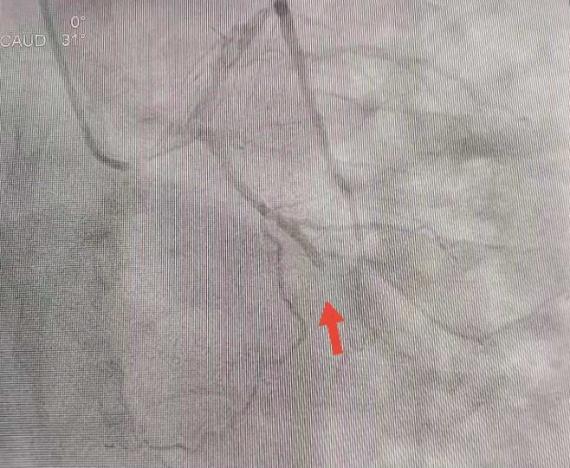

王勇带领介入团队争分夺秒,从血管穿刺到冠脉造影完成仅用时10分钟左右。造影结果显示,刘先生回旋支急性闭塞病变,前降支重度狭窄病变。

团队密切合作,导丝通过、球囊扩张、支架置入,大约5分钟左右,闭塞的血管得以开通,刘先生胸闷胸痛的症状消失,生命危机得以解除。